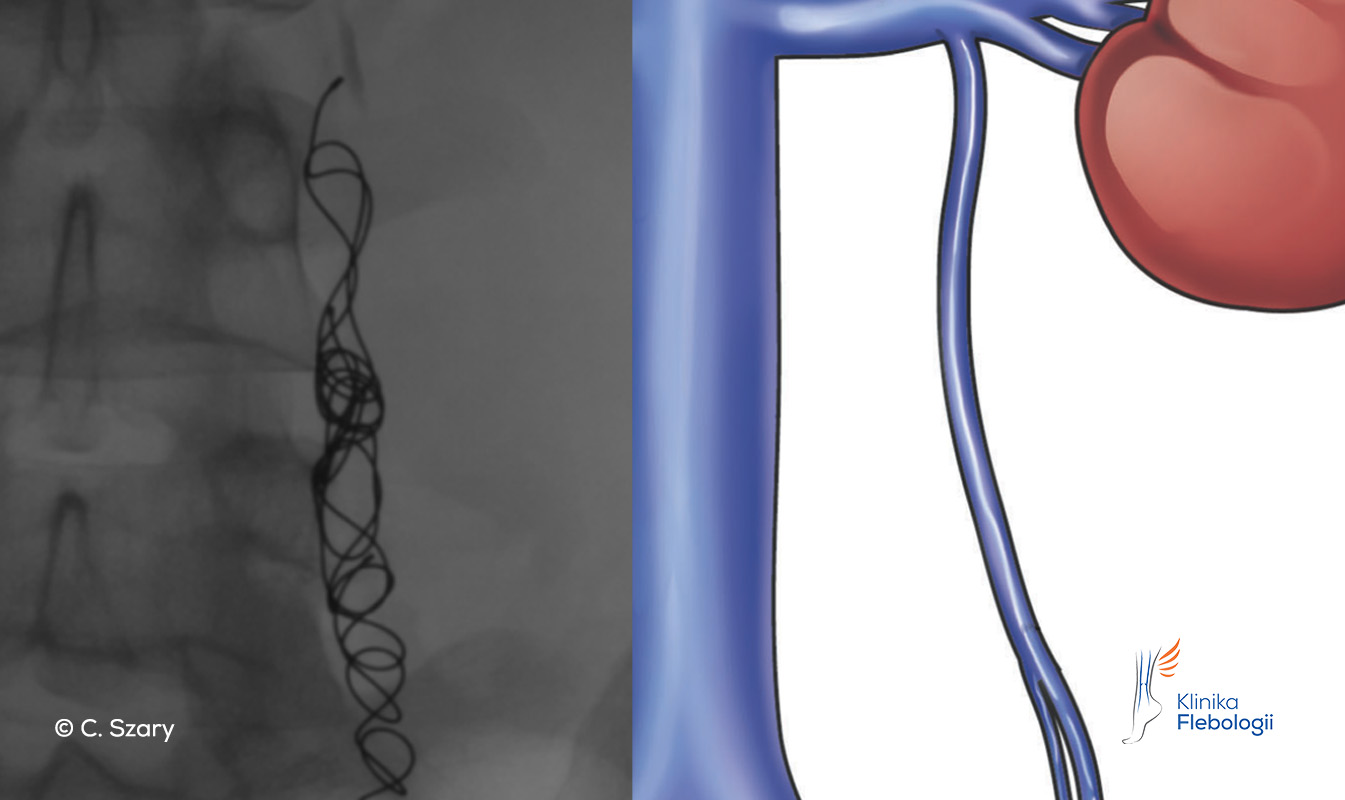

Stan po embolizacji niewydolnej żyły jajnikowej lewej przy użyciu spiral embolizacyjnych

Przy zabiegach embolizacji żylnych lekarze zespołu Kliniki Flebologii wykorzystują najczęściej spienione sklerozanty (zapewniają wysoki poziom bezpieczeństwa), polimeryzujący klej tkankowy oraz nowoczesne spirale (tzw. coile), które są kompatybilne z wysokoteslowymi systemami rezonansowymi (zatwierdzone do pola o sile 3T).

Spirale embolizacyjne stosowane do zamykania niewydolnych żył